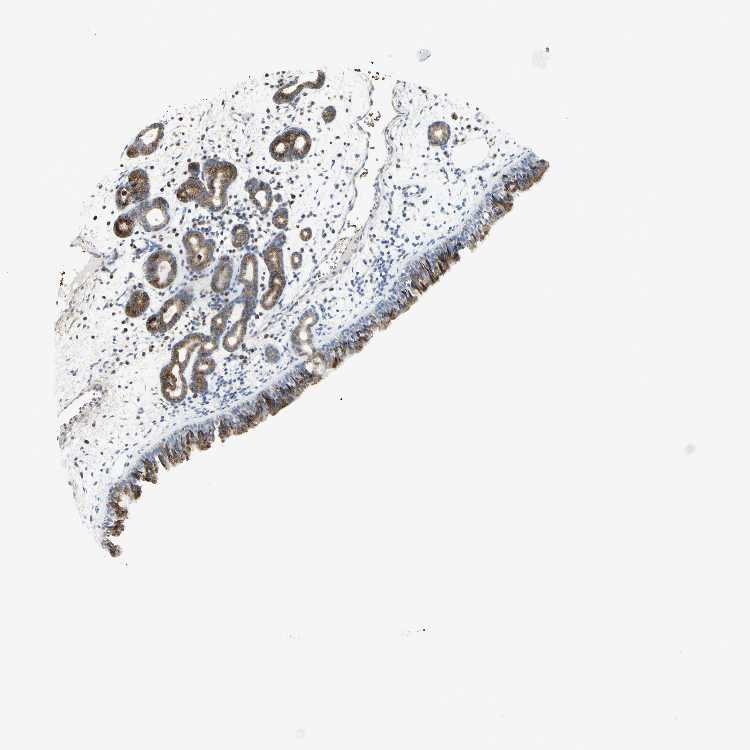

NASOPHARYNX - Antibody stainingi

Antibody staining in the annotated cell types in the current human tissue is reported as not detected, low, medium, or high, based on conventional immunohistochemistry profiling in selected tissues. This score is based on the combination of the staining intensity and fraction of stained cells.

Each image is clickable and will lead to virtual microscopy that enables deeper exploration of all samples and also displays staining intensity scores, fraction scores and subcellular localization as well as patient and tissue information for each sample.

Antibody HPA010664

Respiratory epithelial cells High